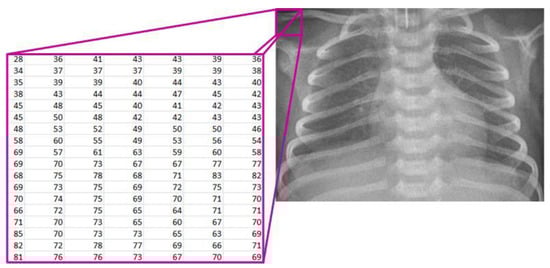

Starting from the image loaded from the corresponding database, it is displayed on the screen and treated mathematically (Figure 2). The image is denoted as [7,19]:

X R M x N ,   w h e r e   X i ,   j 0 ,   255   f o r   i = 1 ,   2 , ,   M   a n d   j = 1 ,   2 ,   ,   N ,

where

• R—the set of real numbers;

• M—the number of rows in the image;

• N—the number of columns in the image;

• X(i, j)—the pixel intensity at position (i, j).

Figure 2. Mathematical representation of the X-ray image.